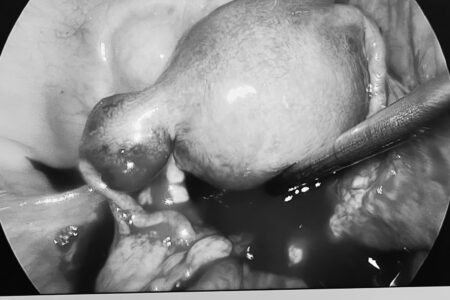

Hình ảnh: Bác sỹ đang thực hiện siêu âm cho người dân

Tại các điểm khám bệnh lưu động, đội ngũ y bác sĩ giàu kinh nghiệm và tận tâm đã triển khai các hoạt động thiết thực:

- Thăm khám & Tư vấn sức khỏe:Người dân được khám tổng quát, kiểm tra các chỉ số sức khỏe cơ bản (huyết áp, đường huyết…), phát hiện sớm các bệnh lý thường gặp ở vùng cao như cơ xương khớp, tiêu hóa, hô hấp.